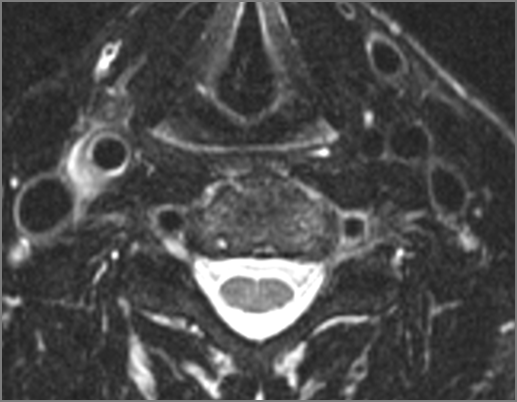

MR: Anatomically focused axial and coronal images through the face and neck region including T1 and T2 weighted acquisitions done with and without gadolinium contrast enhancement and, when indicated, MRV and fat suppression.

Prevertebral and Epidural Spaces

There is edema/abscess within in the prevertebral or paravertebral spaces. [Yes/No]

There is edema/abscess within in the epidural space. [Yes/No]

There is erosive process involving the disc spaces or other components of the spine. [Yes/No]